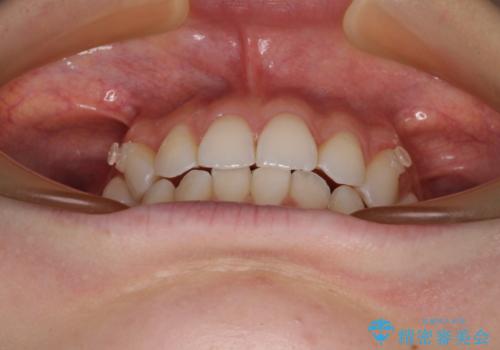

前歯のデコボコと深い咬み合わせ インビザラインできれいに改善

- 前歯のデコボコと下の前歯が隠れてしまう咬み合わせを気にして来院された患者様です。

インビザラインによる上下歯列の拡大と、IPR(歯と歯の間を削る)にるスペースの獲得により、口元のデコボコとディープバイトを改善することとしました。